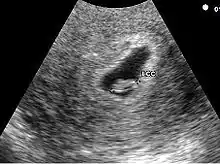

- La visualisation de la vésicule vitelline qui affirme définitivement le caractère ovulaire de l'image échographique.

- La visualisation de la vésicule vitelline est un élément essentiel pour affirmer le caractère ovulaire de l'image et l'évolutivité de la grossesse. Embryologiquement, la vésicule vitelline visualisée correspond à la seconde vésicule vitelline. La vésicule vitelline est toujours visible à 5 semaines et 5 jours par voie endovaginale. Le sac ovulaire mesure en moyenne 8 mm. Par voie abdominale, elle est toujours visible à 7 semaines (le sac ovulaire mesure en moyenne 20 mm). Le diamètre de la vésicule vitelline augmente de 5 à 10 semaines pour atteindre 5 à 6 mm.